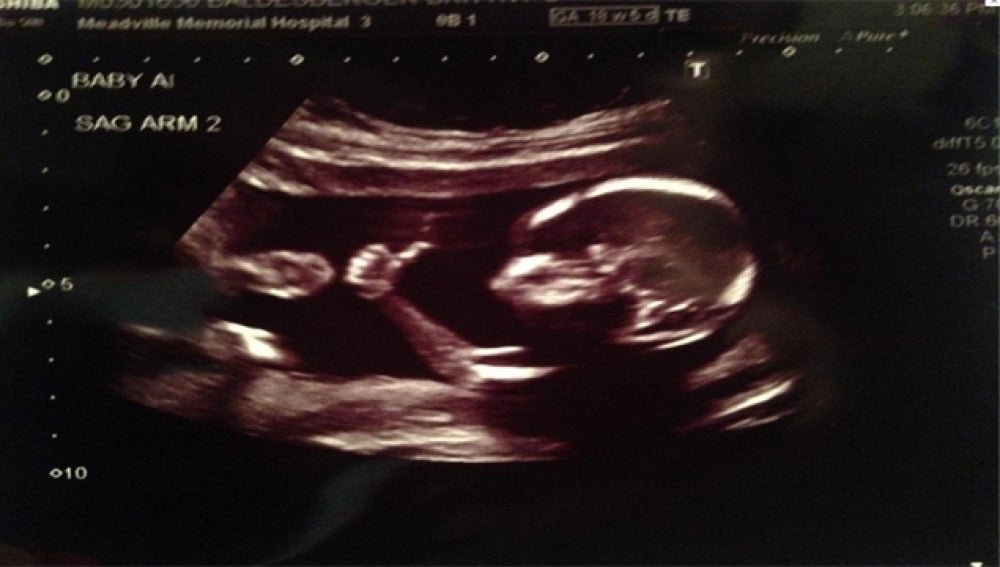

Un feto de 18 semanas levanta el pulgar haciendo el gesto de OK

En una ecografía rutinaria y con sólo 18 semanas un feto levantó el pulgar con la expresión de 'todo va bien' ante el asombro de sus padres. Hasta el momento más de dos millones de internautas han visto la imagen en el perfil de 'Reddit' del progenitor en solo 24 horas.

Solemos entender el gesto de un pulgar hacia  como la expresión de que 'todo va bien'. Con tan sólo 18 semanas un bebé realizó este gesto ante sus papás en una ecografía según publica el diario 'The Independent'.

Ante este gesto, poco habitual para un feto, el padre de la criatura colgó la imagen en su perfil de la red social 'Reddit', donde más de 2 millones de personas ya han visto la imagen. La sorpresa de los internautas fue mayor cuando descubrieron que estos padres estaban esperando gemelos, muchos se preguntaron si el otro bebé estaba de acuerdo con el gesto de su hermano viendo la cómoda postura en la que se encontraba el primero.